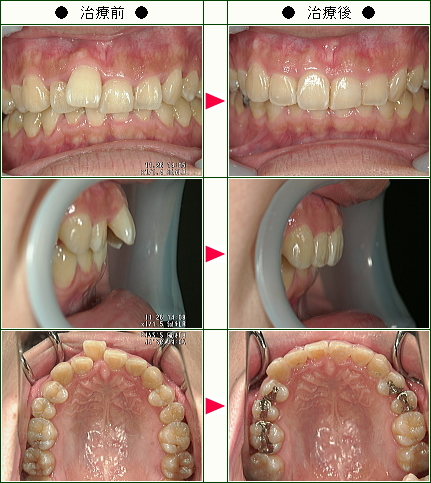

☆歯のデコボコ矯正症例(C・N様 26歳 女性)

結婚式までに綺麗な歯並びにしたくて治療を開始しました。

歯を抜かずに済むということ、短期間で終わるということ、前歯2本だけを治したいという私の希望にぴったりだったのでこの歯科に決めました。

歯を削るのが1番痛そうで不安でしたが、思っていたより痛くなくてよかったです。

毎回、わかりやすく説明をしてから治療を始めてくれるので、安心してまかせる事ができました。

仕上がりも、とても満足しています。

待合室でも、全く待たされることがなく、時間通りに治療が受けられるのも素晴らしいと思います。

家から2時間と少し遠いのですが、この歯科を選んで本当に良かったです。